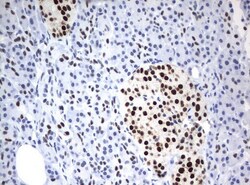

- Submitted by

- Invitrogen Antibodies (provider)

- Main image

- Experimental details

- Immunohistochemical staining of paraffin-embedded Carcinoma of Human lung tissue using anti-ZSCAN18mouse monoclonal antibody. (UM500081; heat-induced epitope retrieval by 10mM citric buffer, pH6.0, 120°C for 3min)